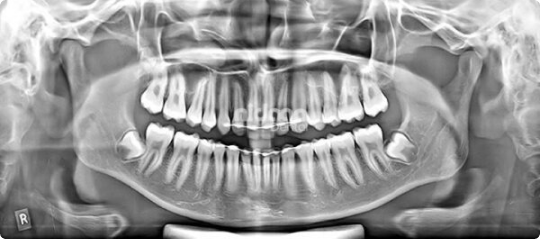

2D Imaging – Digital OPG & Cephalometric Scans

Our digital 2D imaging services include OPG (Orthopantomogram) and Cephalometric X-rays, essential for routine dental diagnostics. With instant digital capture, crystal-clear resolution, and up to 90% reduced radiation exposure, Nidaan’s 2D imaging empowers dentists to detect cavities, cysts, jaw irregularities, and other conditions early, streamlining accurate treatment planning for every patient.

Our digital 2D imaging services include OPG (Orthopantomogram) and Cephalometric X-rays, essential for routine dental diagnostics. With instant digital capture, crystal-clear resolution, and up to 90% reduced radiation exposure, Nidaan's 2D imaging empowers dentists to detect cavities, cysts, jaw irregularities, and other conditions early, streamlining accurate treatment planning for every patient.

2D Imaging - Digital OPG & Cephalometric Scans